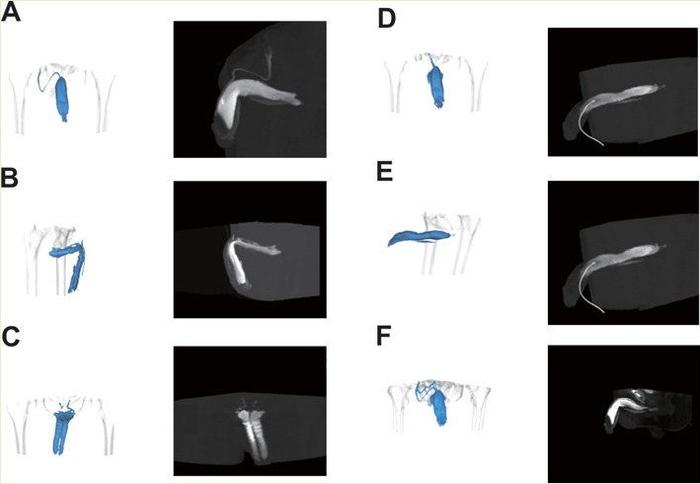

Венозная утечка в кавернозных телах, исследованная с помощью кавернозографии, показывает разные типы утечки: (A) поверхностная венозная утечка; (B) глубокая венозная утечка; (C) краральная венозная утечка; (D) кавернозная утечка; (E) венозная утечка между половым членом и уретрой; (F) смешанная венозная утечка.

Венозная утечка кавернозных тел

Венозная утечка из кавернозных тел, исследованная с использованием обычной кавернозографии, выявляет различные виды утечек: (A) Тип I: поверхностная венозная утечка (визуализация левой наружной подвздошной вены); (B) Тип II: средняя венозная утечка (визуализация уретры и головки полового члена); (C) Тип II: средняя венозная утечка (визуализация правой внутренней подвздошной вены); (D) Тип III: глубокая венозная утечка (визуализация глубоких вен полового члена); (E) Тип IV: смешанная венозная утечка (визуализация левой внутренней подвздошной вены и глубоких вен полового члена).